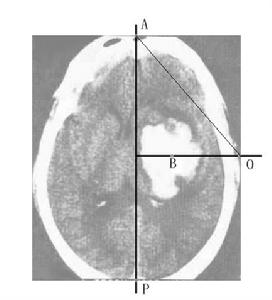

顱內占位性病變,常可通過影象學檢查獲得確診。影象學檢查包括頭顱CT掃描、核磁共振檢查及腦血管造影等。現代影象學檢查可顯示占位性病變的位置、大小、形態、數目,還能觀察到病變內部是否有囊變、壞死、鈣化、出血等。腦血管造影是根據血管的部位、形態的改變、循環時間的改變以及病理血管的出現等,間接了解病變的位置、大致形態、含血管是否豐富等。